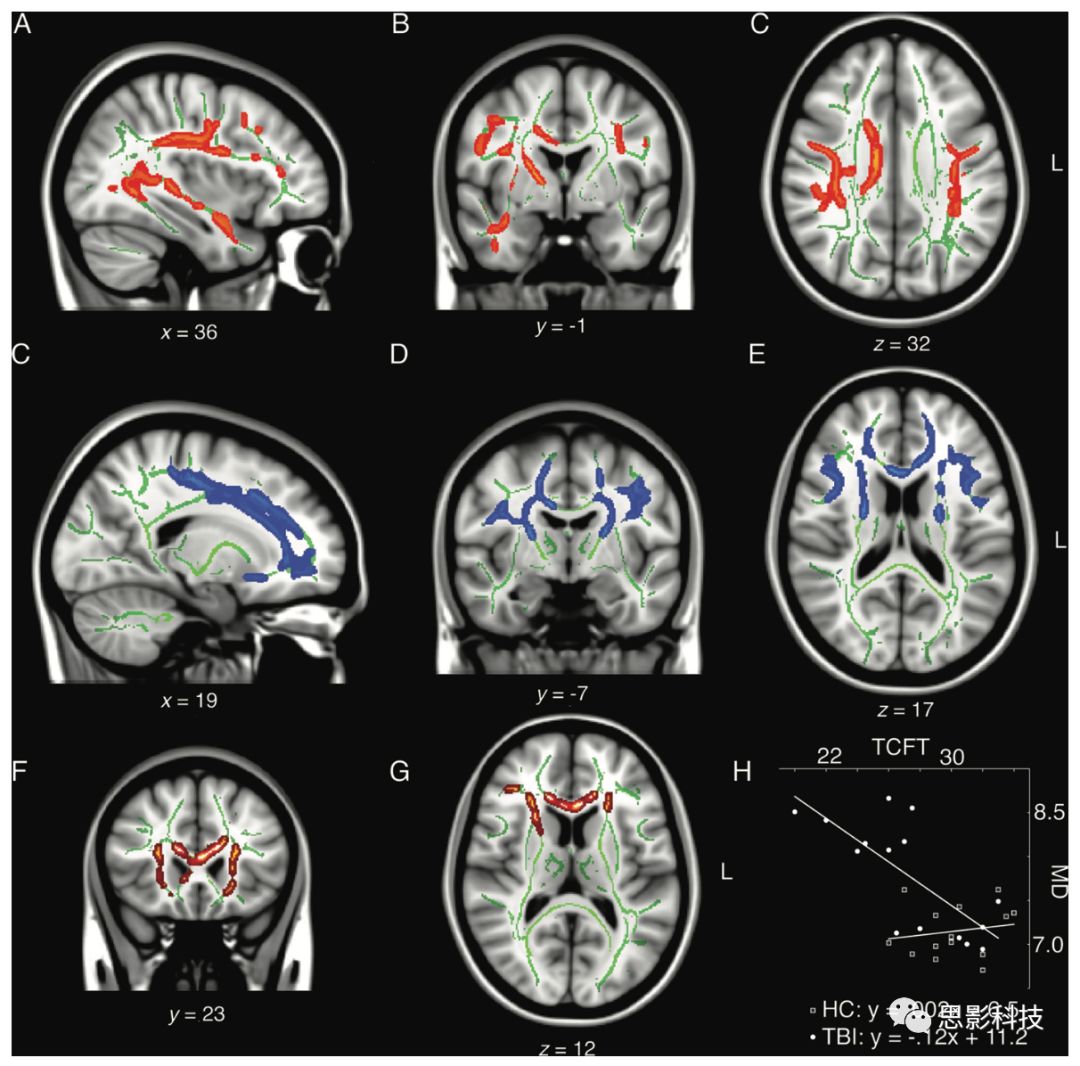

在一項(xiàng)最新的DTI研究中,嘗試控制可能會對腦震蕩長期影響的造成干擾的混雜變量如臨床伴隨疾病或酒精藥物成癮,招募了一批臨床表現(xiàn)正常的退役職業(yè)或半職業(yè)運(yùn)動員,對其進(jìn)行全面的神經(jīng)心理學(xué)測評及彌散加權(quán)成像掃描。這批同質(zhì)性樣本中,半數(shù)退役運(yùn)動員在職業(yè)生涯中遭受過腦震蕩,退役后并未遭受過腦震蕩(平均傷后時間37年),且未遭受過與運(yùn)動無關(guān)的腦外傷(如車禍傷)。采用TBSS分析發(fā)現(xiàn),遭受過腦震蕩的退役運(yùn)動員大腦多個區(qū)域FA減低及MD、RD增高(圖3)。

3. 早年遭受腦震蕩的老年退役運(yùn)動員WM異常(DTI TBSS

A,B,C)經(jīng)歷腦震蕩組與未經(jīng)歷腦震蕩的匹配對照組相比較FA值減低;

C,D,EMD值增高主要位于額葉白質(zhì);(F,G,H)經(jīng)歷腦震蕩組情景記憶功能下降與MD增高的相關(guān)

根據(jù)動物實(shí)驗(yàn)研究,這些異常被認(rèn)為反映了軸索損傷及髓鞘病理改變。從臨床意義上,這些WM完整性與亞臨床認(rèn)知、運(yùn)動功能下降存在關(guān)聯(lián)。這些觀察結(jié)果與近期一項(xiàng)通過排除標(biāo)準(zhǔn)嚴(yán)格控制混雜因素的結(jié)果一致。該研究將曾遭受過多次腦震蕩的退役職業(yè)運(yùn)動員鉤束、灰質(zhì)異常與行為及認(rèn)知下降進(jìn)行關(guān)聯(lián),并存在相關(guān)。這些發(fā)現(xiàn)提示,早年遭受腦震蕩會影響隨后數(shù)十年老化的結(jié)構(gòu)及功能衰退。這些結(jié)果提示年輕無癥狀運(yùn)動員潛在的WM損傷持續(xù)甚至隨時間加重,最終導(dǎo)致認(rèn)知、運(yùn)動功能下降。